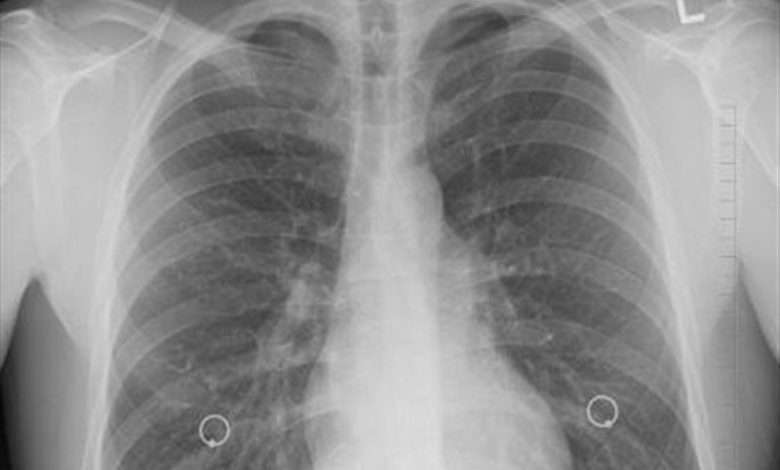

وی عنوان کرد: سرطان ریه یکی از پنج سرطان کشنده در جهان است. به دلیل تهاجمی بودن، زمان کمی برای درمان باقی میگذارد و متاسفانه بسیاری از بیماران در سالهای اول فوت میکنند. میزان ابتلا در بخش مردان حدود 12.7 در هر صد هزار نفر و در میان زنان رقمی کمتر از مردان است. در استان گلستان اما میزان شیوع این بیماری بالاتر است و در مردان میزان ابتلا 21.3 در هر صد هزار نفر (بسیار بالاتر از میانگین کشوری) و در میان زنان 5.21 در هر صد هزار نفر است.

روشندل با اشاره به عوامل خطر شناخته شده سرطان ریه گفت: مصرف سیگار (ریسک بسیار بالا)، در معرض دود سیگار بودن، مصرف الکل و نوشیدنیهای الکلی، مواجهه شغلی با تشعشعات (مثل برخی محیطهای بیمارستانی یا صنعتی)، آلودگی هوا و آب، تریاک (به عنوان یک عامل خطر مهم و خاص در کشور) است.